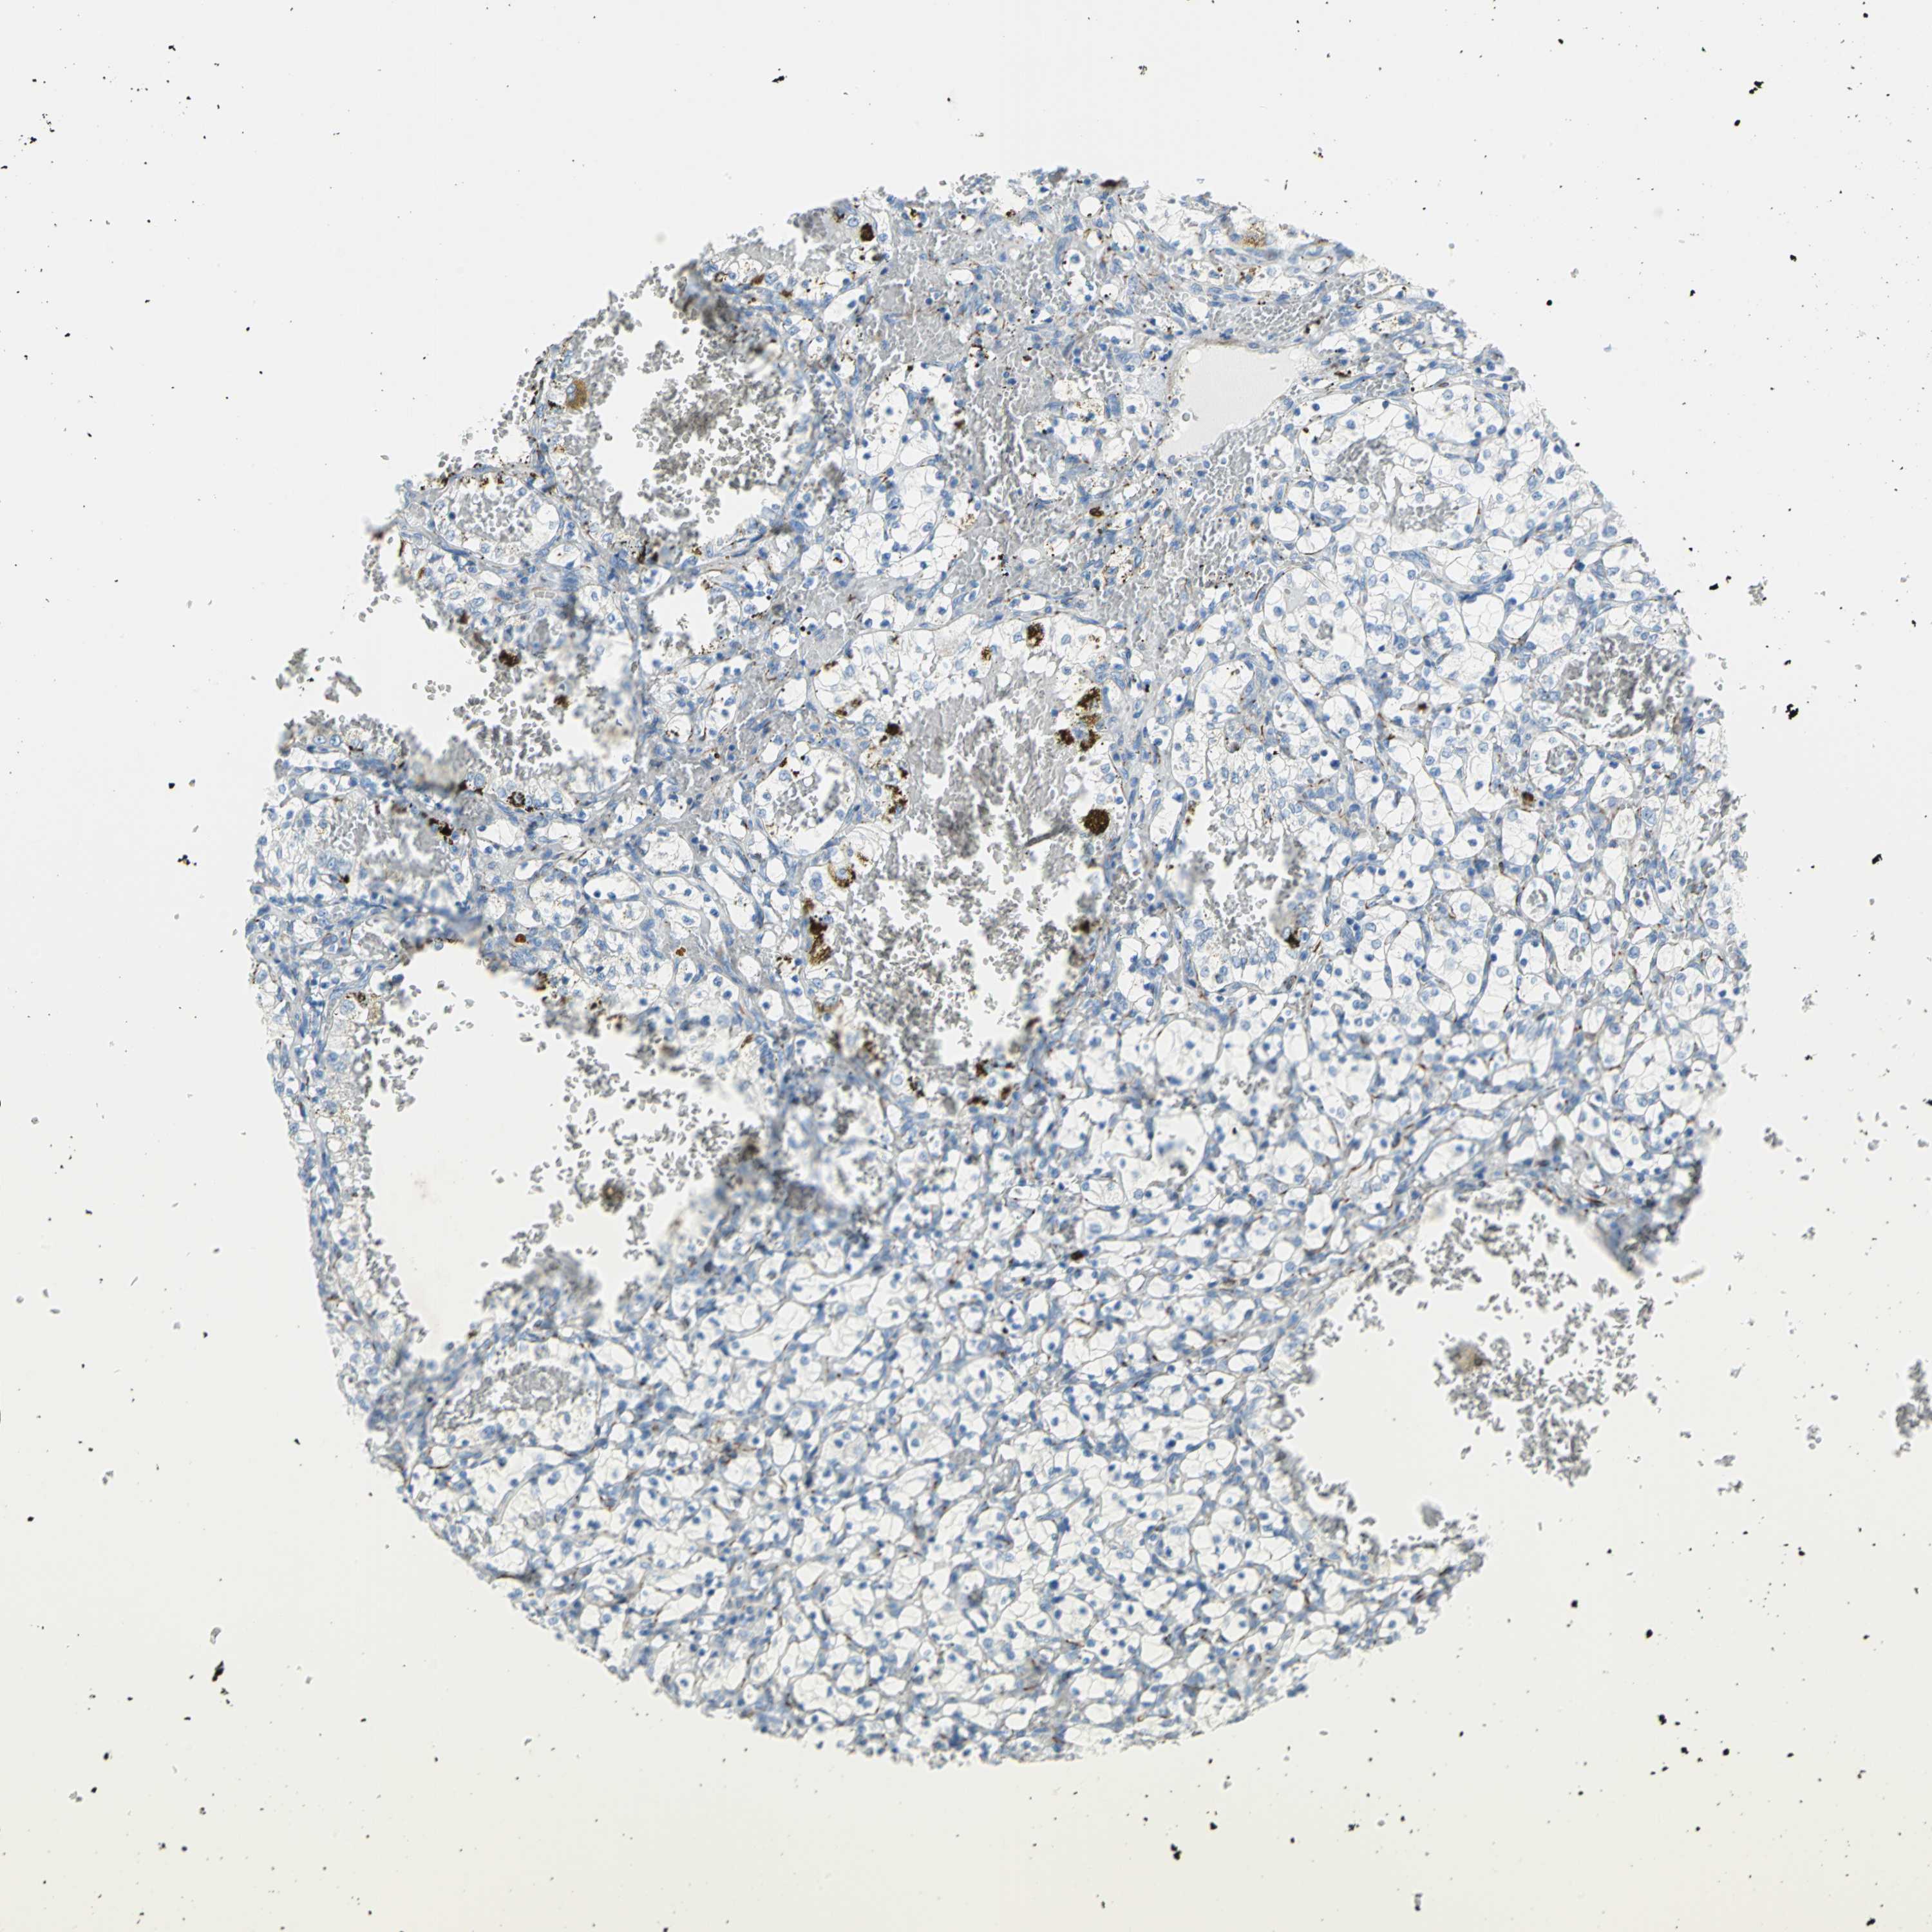

CANCER RENAL CANCER Show tissue menu

KICH TCGA KIRC TCGA KIRC VALIDATION KIRP TCGA PROTEIN RCC CPTAC PROTEIN EXPRESSION